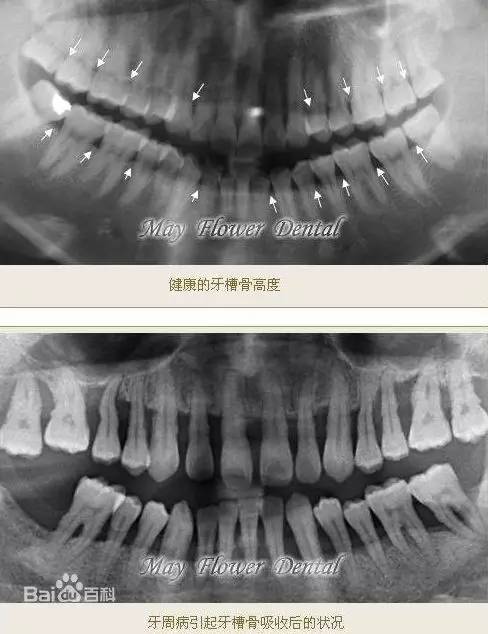

▎牙槽骨吸收

牙槽骨是上下颌骨包围和支持牙根的部分,牙槽骨的吸收会使牙齿的支持组织丧失,牙齿逐渐松动,最终脱落或拔除。严重的牙周病就会引起牙槽骨吸收。

图片来自百度百科

在整牙的过程中,牙齿持续受力,会使得部分牙槽骨吸收萎缩。成年人矫正、本身就有牙周炎的情况更容易遇到这种问题。▼